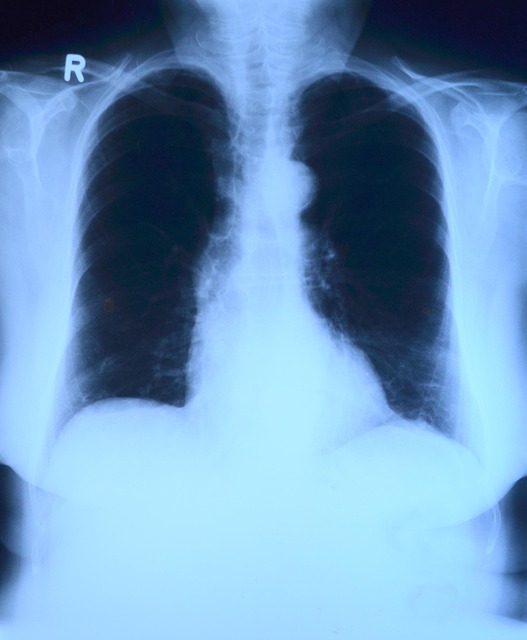

pixabay.com